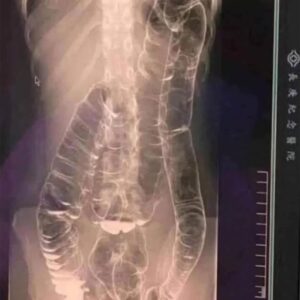

Severe Constipation and Toxic Megacolon: Causes and Solutions

Although constipation may seem like a minor inconvenience, ignoring it for extended periods can lead to serious health complications. A striking real-life case demonstrates just how dangerous…